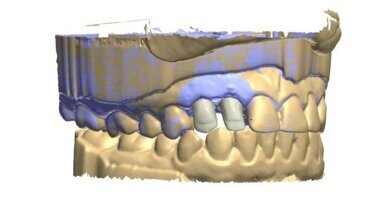

55-letni pacjent, po odbudowie odcinków bocznych mostami ceramicznymi w sposób klasyczny, zgodził się na zastosowanie cyfrowych technik rejestracji celem wykonania odbudowy protetycznej odcinka przedniego (Ryc. 3). Po wykonaniu preparacji filarów: 13, 12, 11, 21, 22 i 23 zarejestrowałem cały łuk górnych zębów za pomocą skanera wewnątrzustnego (Ryc. 4). Następnie dokonałem rejestracji całego łuku dolnych zębów (Ryc. 5).

Kolejnym etapem jest zarejestrowanie okluzji. W tym celu prosimy pacjenta o zagryzienie zębów i skanujemy grupę 2-3 zębów dolnych wraz z przylegającym do nich dziąsłem oraz grupę 2-3 zębów przeciwstawnych(górnych), także z przylegającym dziąsłem.Skaner automatycznie składa zeskanowane wcześniej łuki górny i dolny w prawidłowym okluzyjnym położeniu (Ryc. 6).

Szybkie, wygodne dla pacjenta, cyfrowe zarejestrowanie warunków w jamie ustnej daje bezpośredni dostęp do trójwymiarowego obrazu (Ryc. 16-18). Dzięki temu możemy przeprowadzić wstępną analizę łuków zębowych w różnej projekcji i w różnym powiększeniu, obraz na ekranie skanera można powiększać i obracać. W klasycznym postępowaniu taka analiza możliwa jest dopiero po kilku godzinach. Na ekranie skanera możemy skorzystać z funkcji rysowania linii. W oparciu o linie pionowe (zielone linie na rycinach) uzyskujemy informację o prawidłowej preparacji zębów (Ryc. 19 i 20).